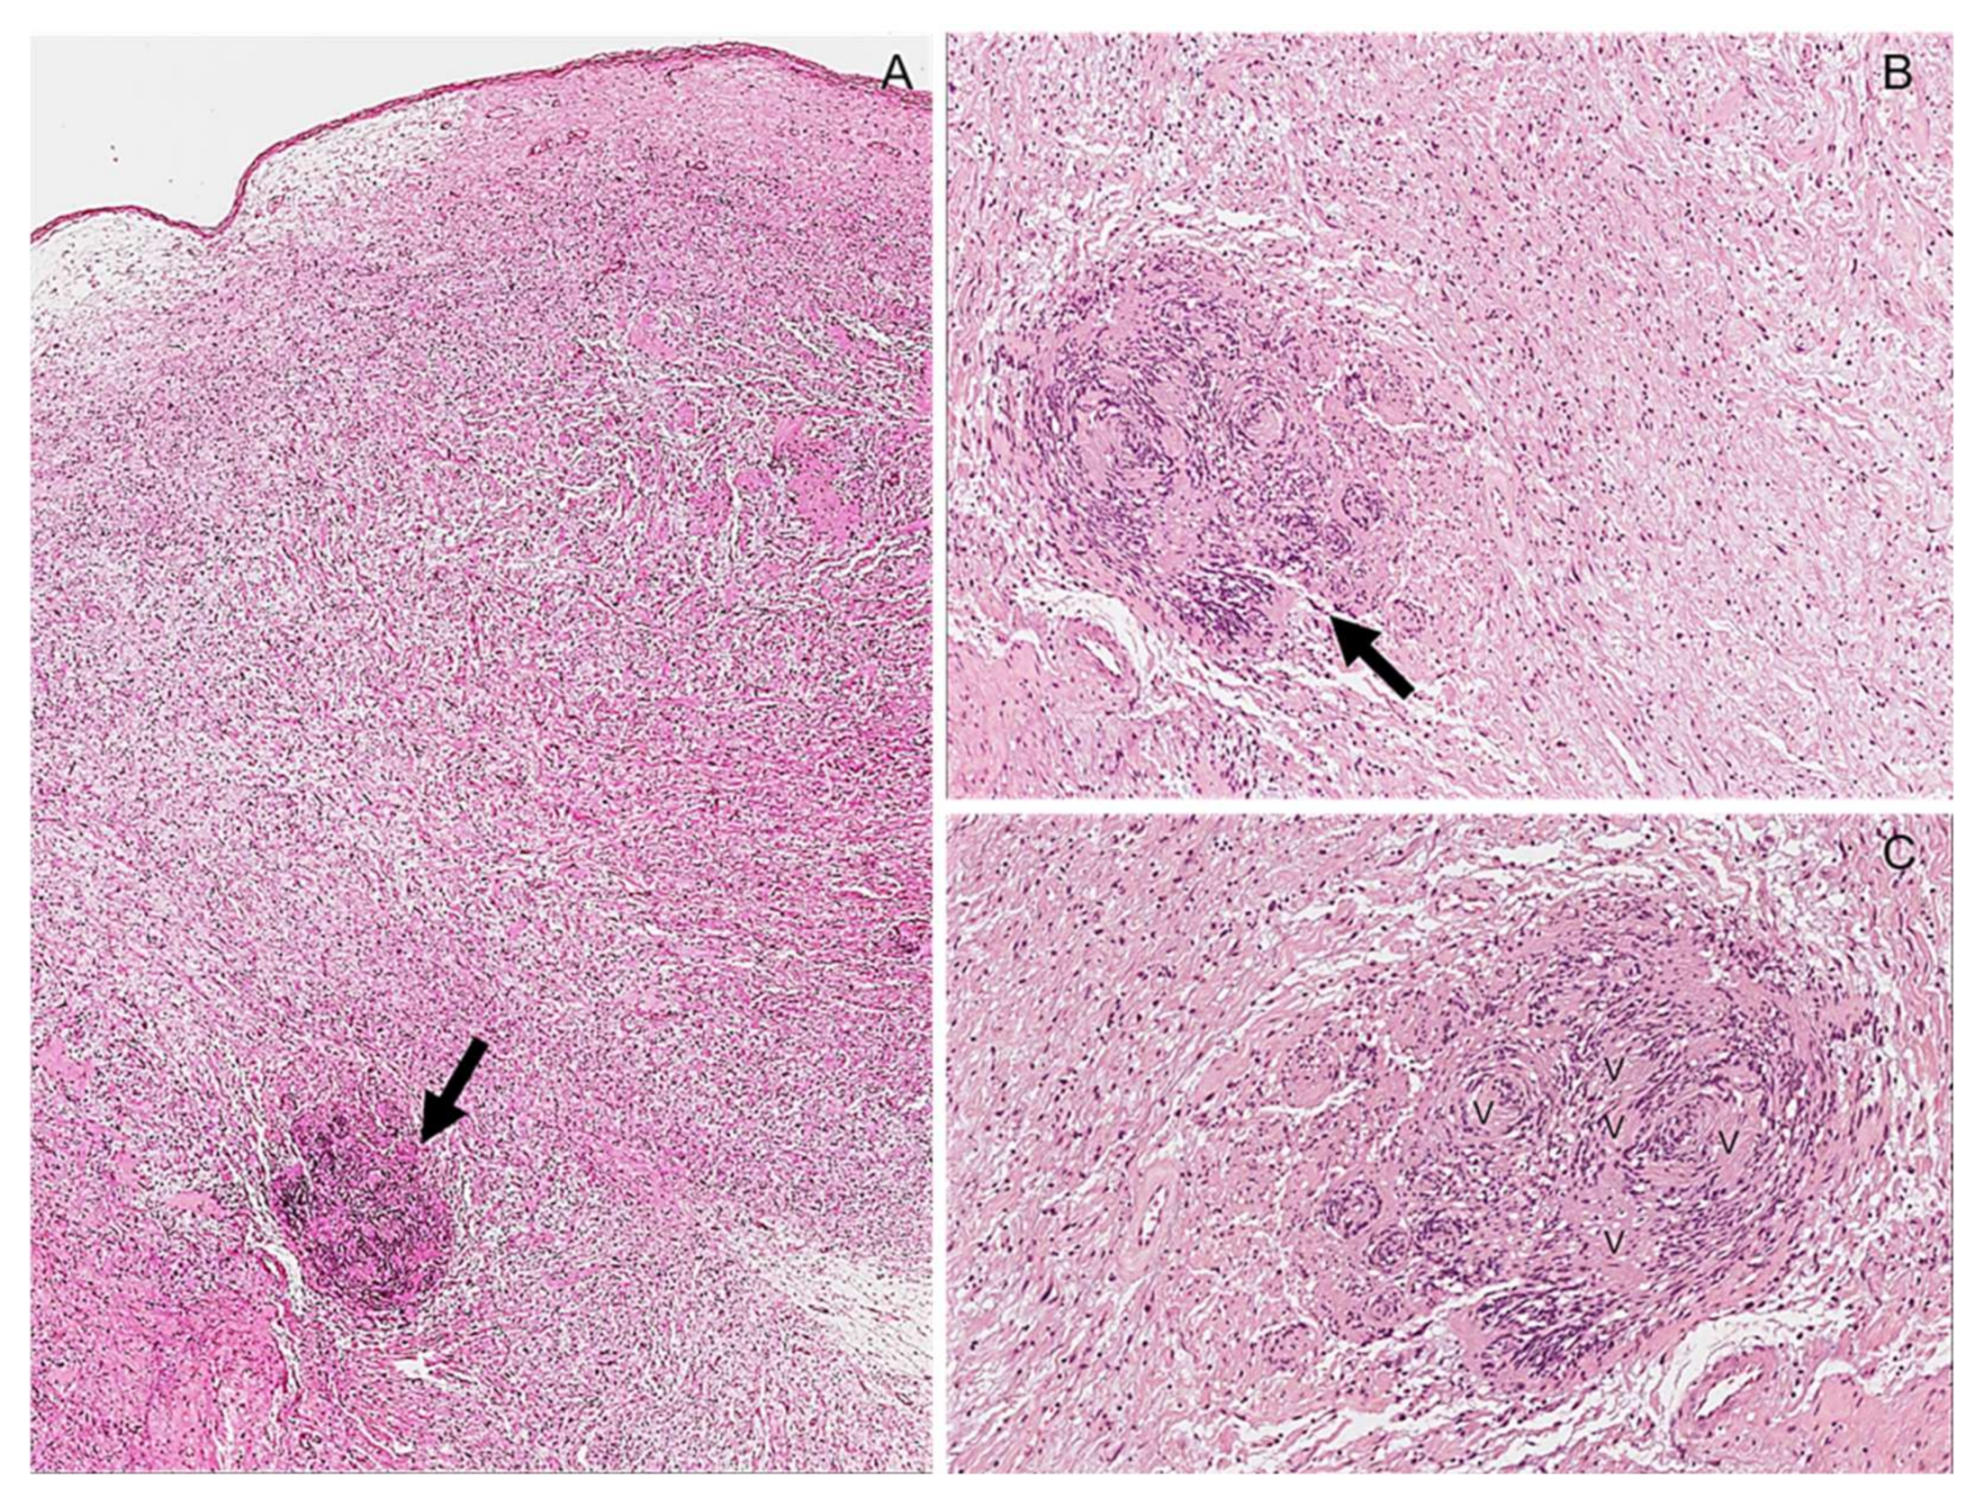

Definition |

|

Clinical Features |

Gross Pathology |

Histopathology |

Immunohistochemistry |

Treatment/Prognosis |